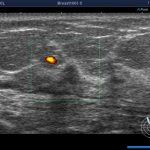

検査2乳腺エコー(超音波検査)

エコー検査は、乳腺用の超音波診断装置を用いて、乳房内部に出来たしこりについて良性、悪性を調べる検査です。

悪性腫瘍である乳がんが存在する場合、高い確率で発見することが出来る検査です。

また、若年者の乳腺は、マンモグラフィ(乳房X線検査)では分かりにくい場合が多く、エコー検査が有効です。 -

超音波検査は、マンモグラフィでは乳腺が発達していて病変を見つけにくい方(高濃度乳腺)、あるいはちいさな腫瘤を見つけるのに有効です。